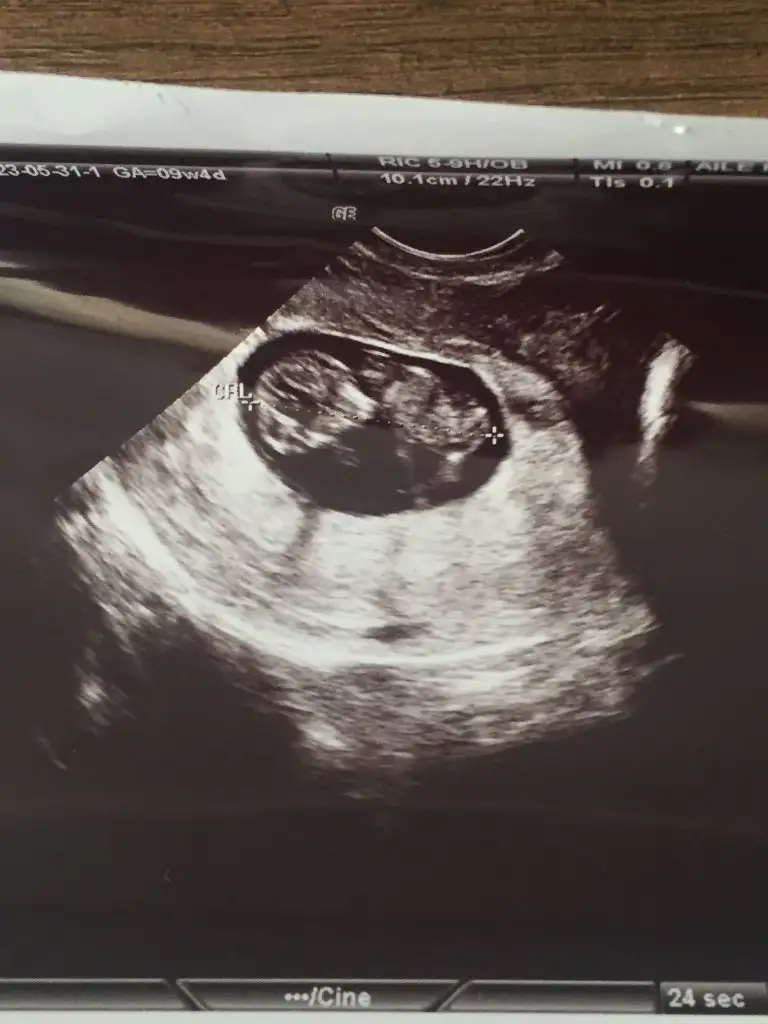

Kızlar ikili test sonucum çıktı doktoruma da ulaşamadım anlayan varsa bakabilir mi

• IMG_20230531_145058.webp

IMG_20230531_145058.webp

38,9 KB · Görüntüleme: 69